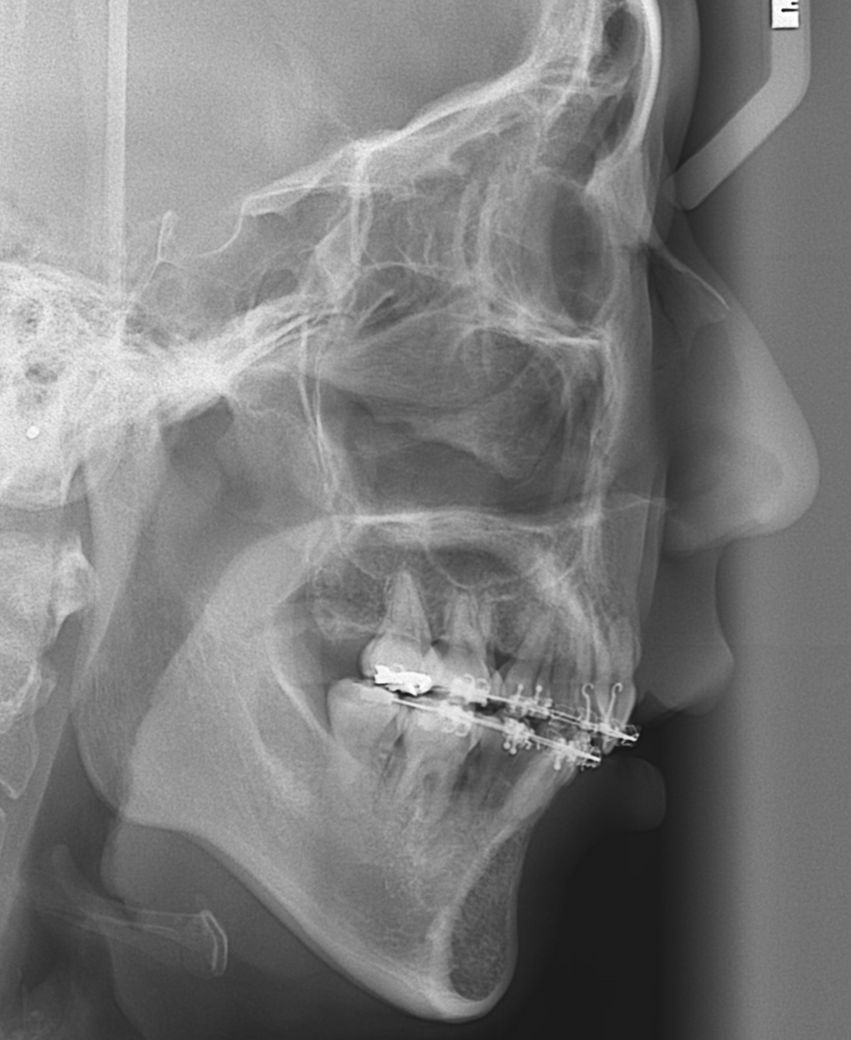

교정 중인데 옥니 맞는지 확인 좀 부탁드려요

교정 얼마 안 남았다고 하는데 상악 앞니가 너무 옥니 같거든요? 근데 병원에선 그정돈 아니고 정상수준 이라는데 제 눈엔 너무 옥니 같아요... 제가 과하게 오바하는 건지 확인 부탁드립니다...

교정은 주관적인 생각이 중요하기 떄문에 환자분이 그렇게 생각하신다면 치과에 말씀을 하셔서 수정을 하시는게 좋을것같습니다. 엑스레이 상으로는 크게 문제가 잇어 보이진 않습니다.

상악 잇몸뼈와 위 앞니의 각도가 말씀하신것처럼 살짝 옥니에 가까운 것 같으나 정상범주이내일 수 있습니다